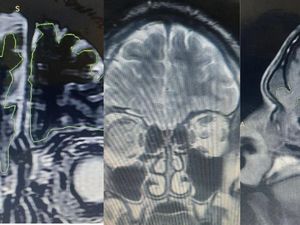

Cerita Pemuda yang Tak Sadar Otaknya 'Bocor' Selama 6 Tahun

Seorang pria Suriah mengalami otak 'bocor' selama enam tahun setelah kecelakaan. Setelah perawatan, gejala seperti sakit kepala dan kejang akhirnya hilang.